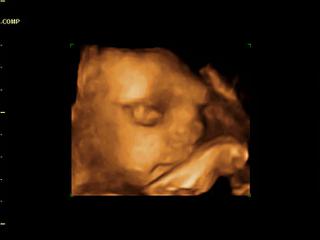

Dnes sme boli na 4d v saci. mame aj nejake videjka aj fotecky ale nie su az v takej kvalite, lebo mam placentu na prednej stene a tym je mala natlacena na placente a pred nou je menej plodovej vody a este mala aj rucicku pred tvarickou ale nevadi aspon nieco mame a sme hlavne radi, ze je ok. pripajam fotecku.